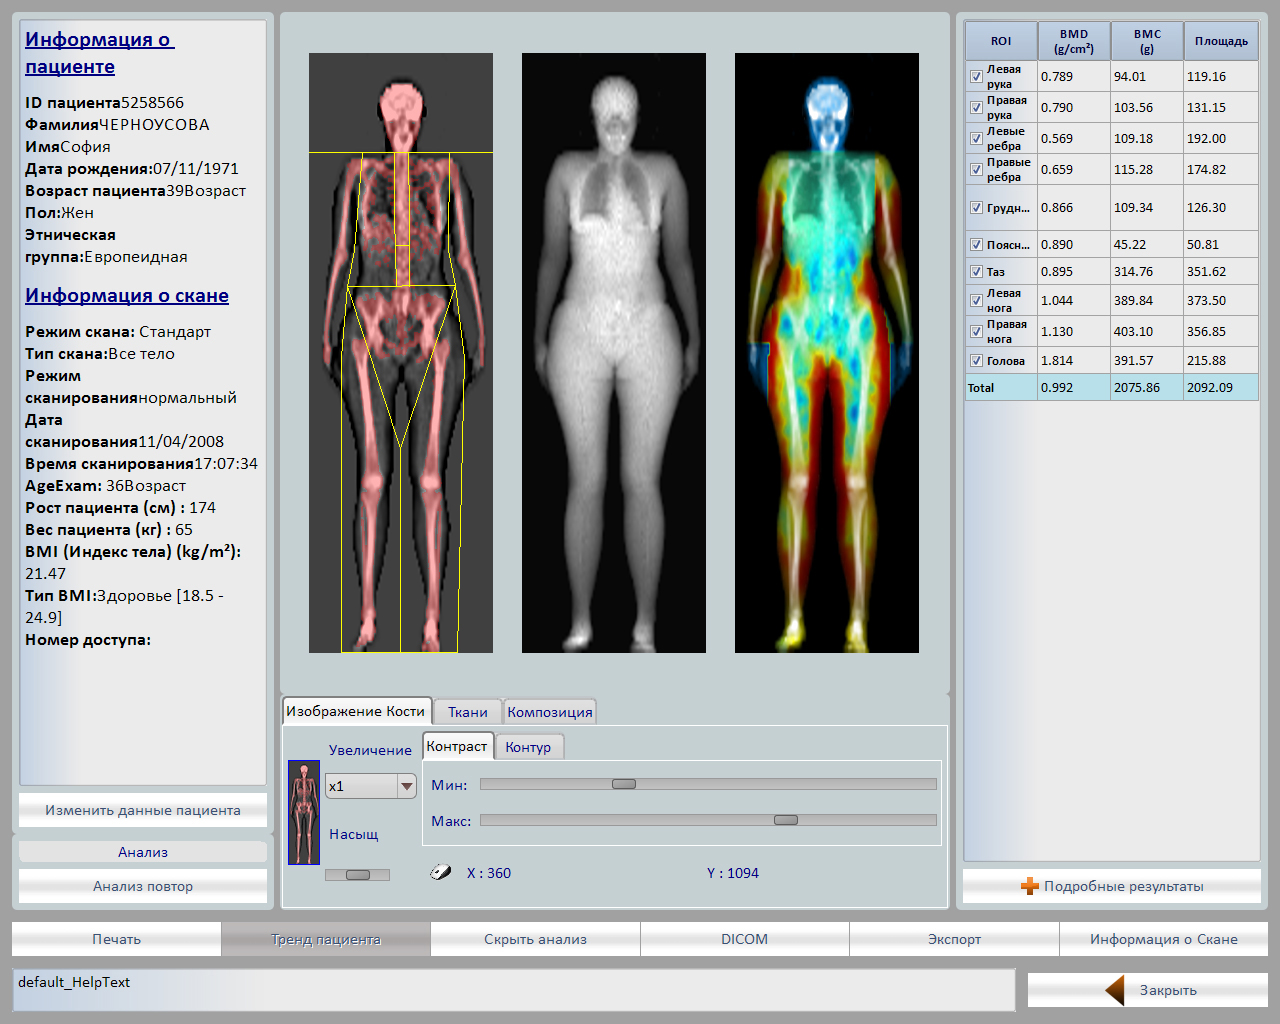

Главной особенностью аппарата является широкий спектр возможных исследований: поясничный отдел позвоночника, проксимальный отдел бедренной кости, кость предплечья, обследование позвоночника в боковой проекции, боковая проекция оценки позвонков, возможность проводить исследования состава тела.

- Программа «Все тело» с возможностью построения тренда тощей, костной и жировой массы

Данный режим полезен для получения информации:- Ожирение,

- Развитие отклонений,

- Первичный и вторичный гипертиреоз,

- Анорексия,

- Мышечная дистрофия

- Синдром Кушинга